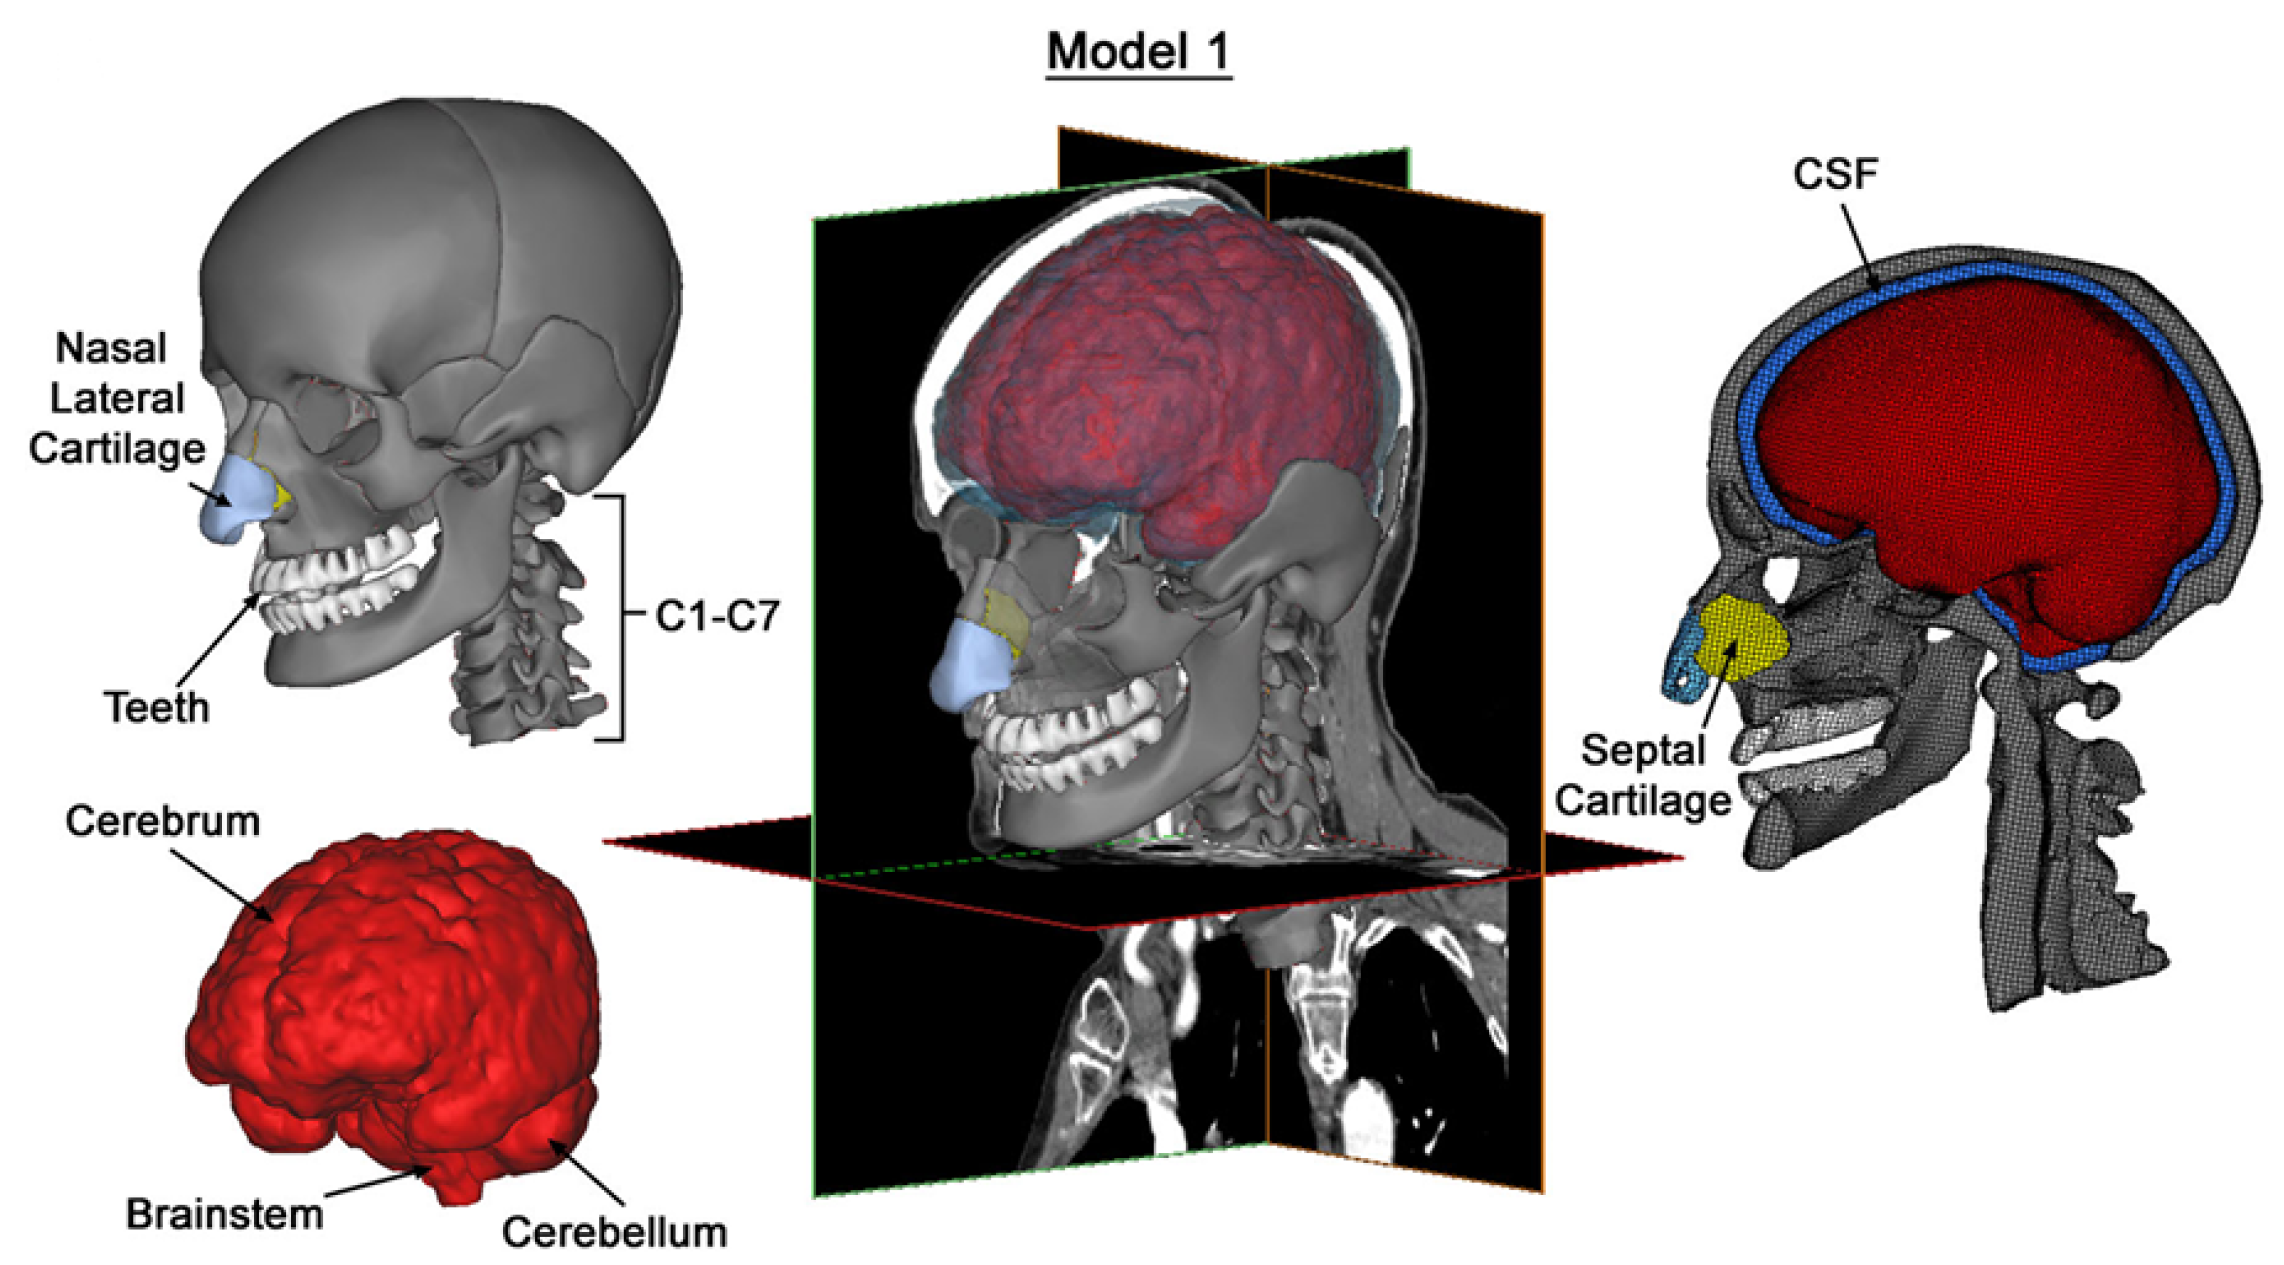

2.1. Finite Element Model of the Head

2.1.1. Model Construction